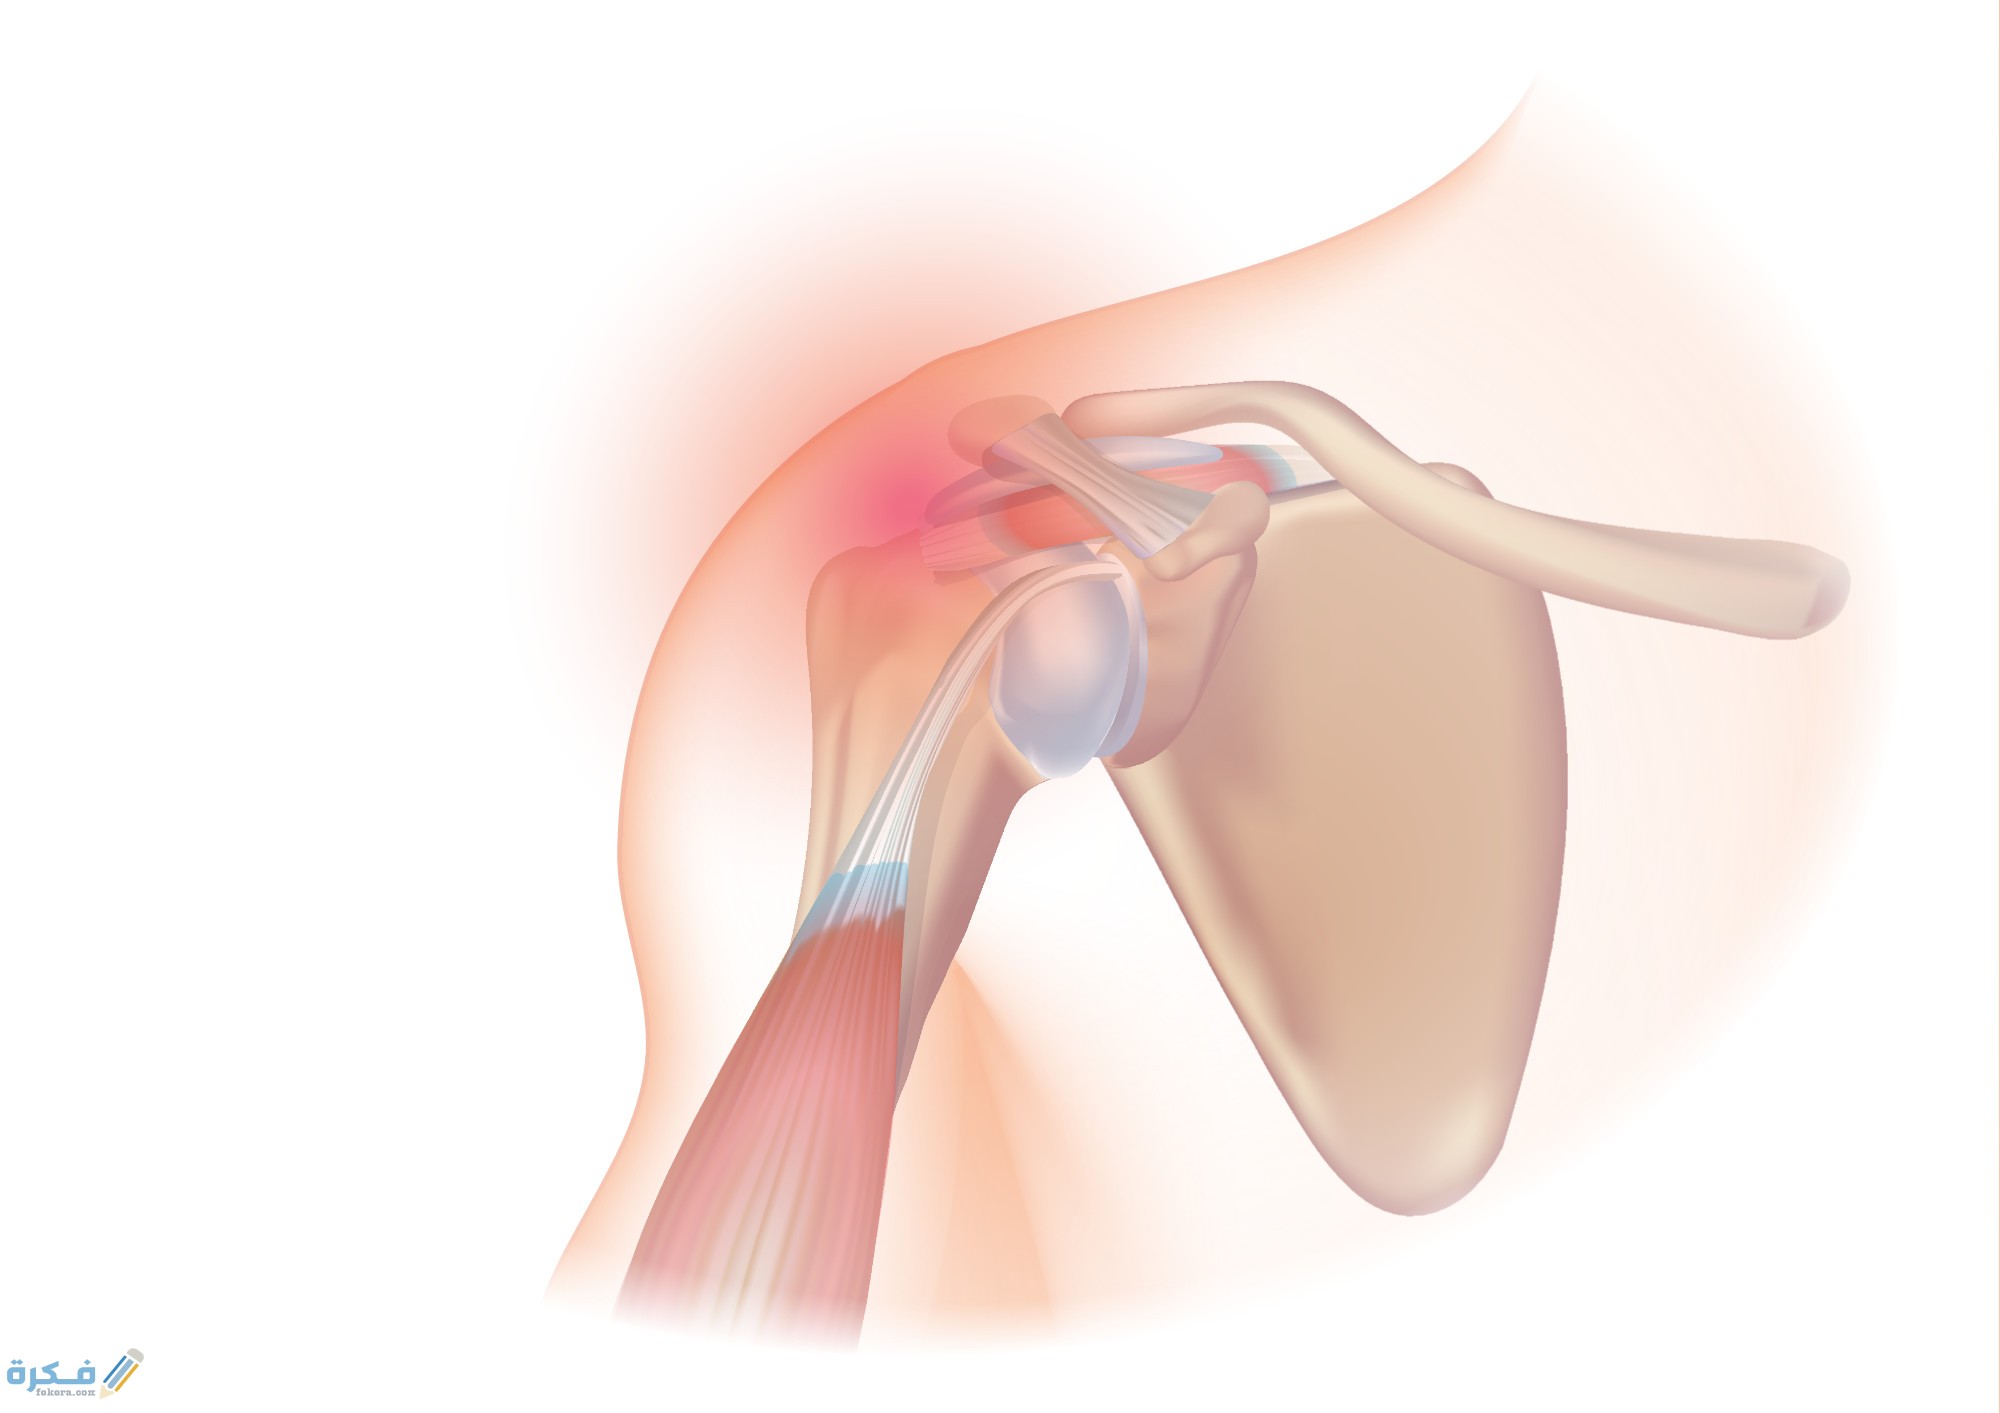

أكمل القراءة »كم يستمر التهاب أوتار الكتف وطرق علاجه من خلال موقع فكرة يعد التهاب أوتار الكتف من الامراض الاكثر شيوعا خلال…